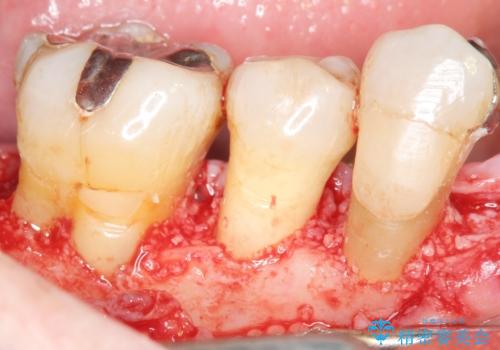

骨吸収の進行している右下臼歯部に、再生療法(骨を増やす手術))を行いました。

再生療法から1年後、リエントリー手術により骨の再生を確認し、骨外科処置(骨を平らにして歯周ポケットの根本的な改善を図る処置)を行いました。